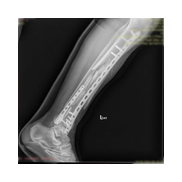

Görüntüleri büyütmek için resmin üstüne tıklayınız.